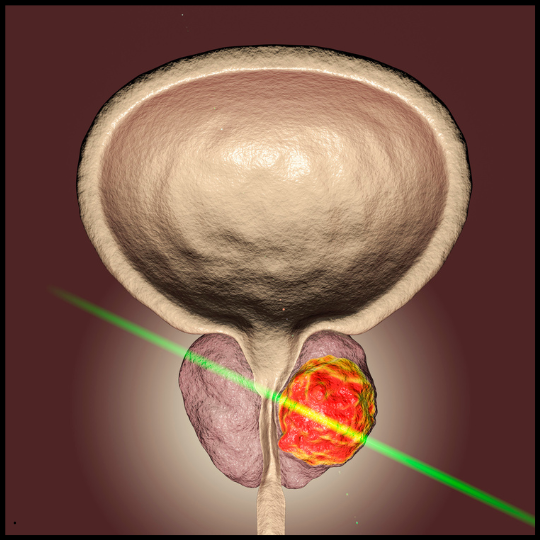

The real problem lies within the prostate, where pressure and inflammation accumulate, creating discomfort and triggering frequent urges to urinate.

Over time, this tension builds up, affecting the nerves that control urination. These nerves are supposed to send signals that allow you to urinate when it’s truly necessary.

But with this constant pressure, they remain overstimulated, causing those frequent urges even when your bladder isn’t full.

This ongoing stimulation overwhelms your body, making you feel like you constantly need to go, even if there’s no real need.

Recent studies show that this inflammation is a key factor behind urinary urgency in men with prostate issues. And once this pressure builds up, it doesn’t resolve on its own.

That’s why, no matter how many treatments you try—whether it's medications, diet changes, or even physical exercises—none of them can offer lasting relief.

As long as this inflammation persists, the discomfort and urgency will continue. Traditional treatments only mask the symptoms.

If left untreated, this pressure can cause the condition to worsen over time, leading to more severe issues, like urinary incontinence.

That’s why reducing this pressure is so crucial. Once it’s relieved, your urinary function can return to normal, and those frequent urges will subside.